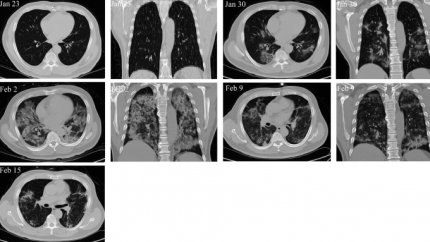

Фото: aginganddisease.org

Изображения компьютерной томографии (КТ) грудной клетки пациента с подтвержденным диагнозом COVID-19 в критически тяжелом состоянии. В динамике: 23 января показатели пневмонии не наблюдались, 30 января обнаружено наличие симптома «матового стекла» и пневмонической инфильтрации. Трансплантация клеток была проведена 31 января. 2 февраля пневмония уже поразила все легкое. 9 февраля инфильтрация в значительной степени исчезла. 15 февраля на месте осталась лишь небольшая область «матового стекла».